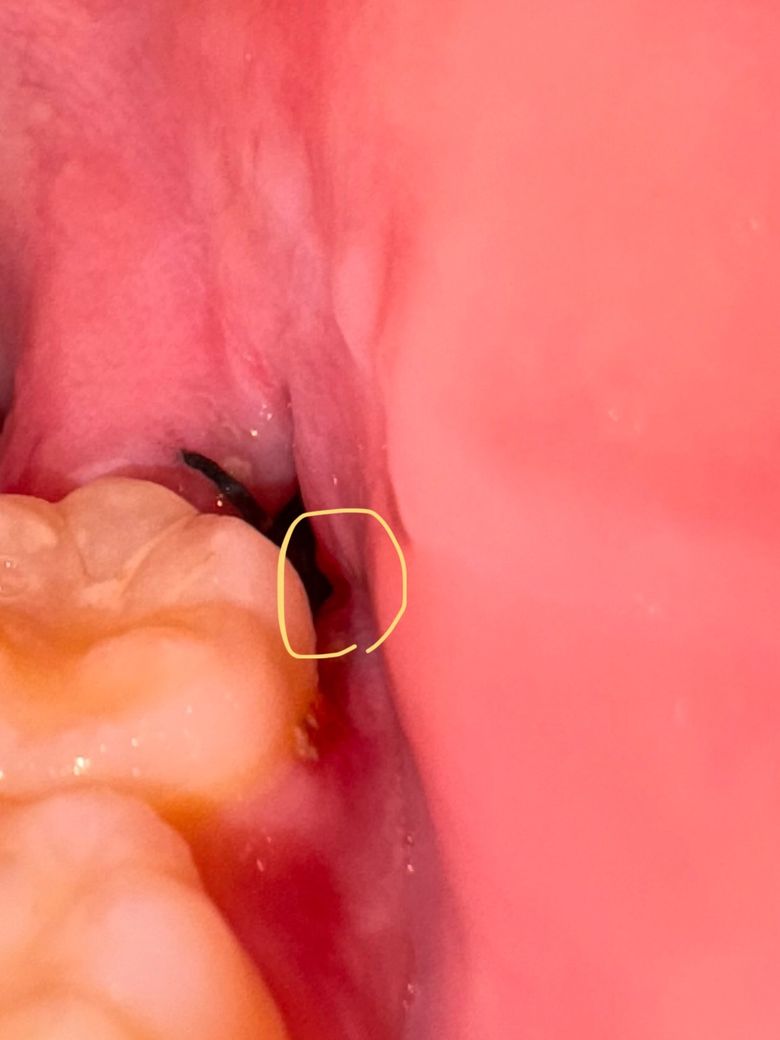

매복 사랑니 발치 후 절개 부분 실밥 풀림

사랑니 발치하고 오늘 6일차고 내일 실 풀러가는데 실로 꿰먀둔곳 보니까 실이 한쪽에만 걸려있어요. 반대쪽 보니까 뜯긴거같은데 괜찮나요? 피는 안나는거같은데 하얀 이물질들이 껴있어서 빼긴했어요 아프진않고 턱부분이 뻐근하기만 해요

• 1번 째 사진

이물질은 계속 잘 빼주시고요 피 안나면 실밥은 크게 의미없습니다 다만 상처부위가 벌어지면 잇몸 회복이 더뎌지니 너무 입 크게 벌리지 마세요